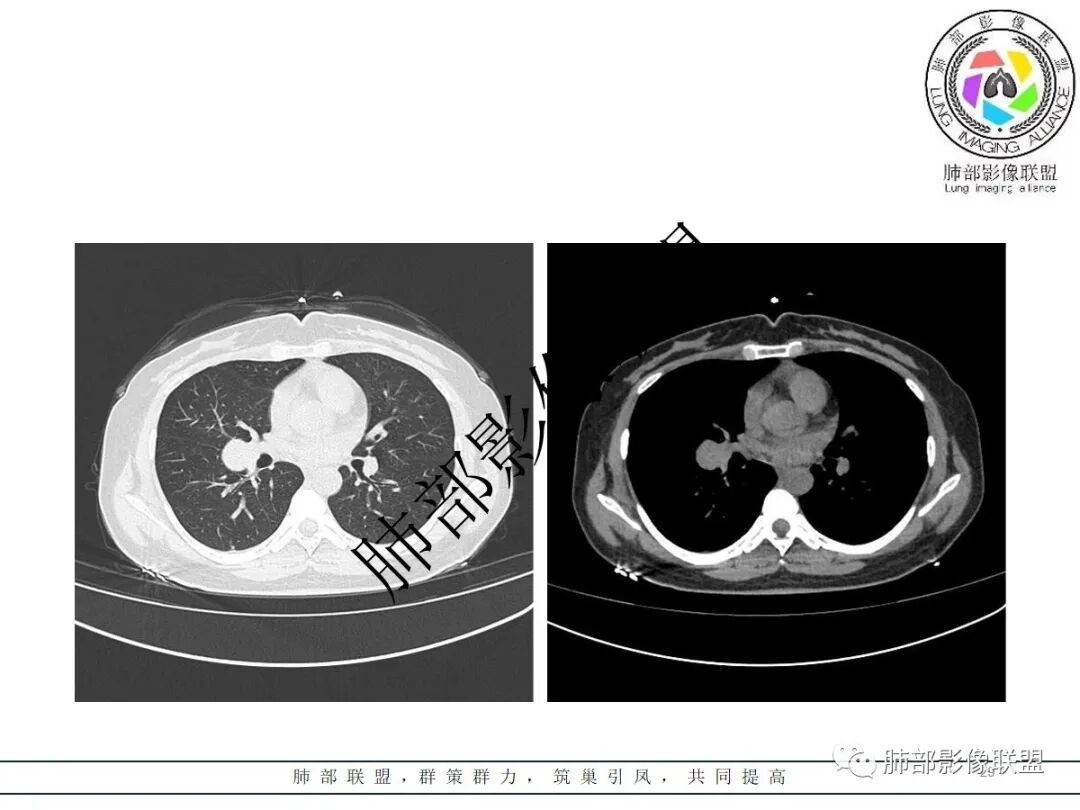

右肺门类圆形实性肿块,边缘光滑,无分叶毛刺,跨叶,推移血管,密度均匀,增强延迟强化相对明显,未见坏死及血管造影征。

右近肺门类圆形肿块,边缘光滑,密度均匀,压迫邻近肺动脉,跨叶间裂,持续不均匀强化,内见血管影,肺门纵隔淋巴结未见肿大,考虑PSP,鉴别类癌。

鉴别诊断:PSP、SFT类癌,肿块主要与血管关系密切,与气管关系不大,故类癌可能性小,肿块渐进性均匀强化,可见血管贴边征、肺动脉为主征,中年女性患者,首先考虑PSP,肿块与叶间裂关系比较密切,不能除外SFT,但与血管关系更为密切,SFT往后排一下。

2.右肺水平叶裂斜叶裂肺门交界区类椭圆形块影,表面光整,未见分叶毛刺及棘状突起,未见邻近结构牵拉。与邻近支气管无关联。

3.病灶密度均匀,未见液化坏死、钙化及脂肪低密度。轻度强化,可见纤细血管影蜿蜒穿行。右肺动脉推移变形,未见侵入或充盈缺损。

3)硬化性肺细胞瘤(PSP)可以血管贴边,常常强化比较显著。

4)发生于肺表面(近脏层胸膜或叶间裂),强化不显著,可见穿行血管,与本例的符合程度是最高的。